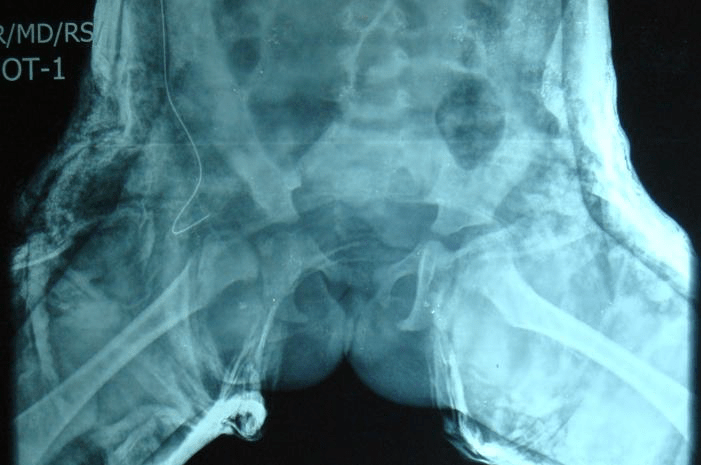

1. 18 months old Pre op & Post-op (OR & Spica)